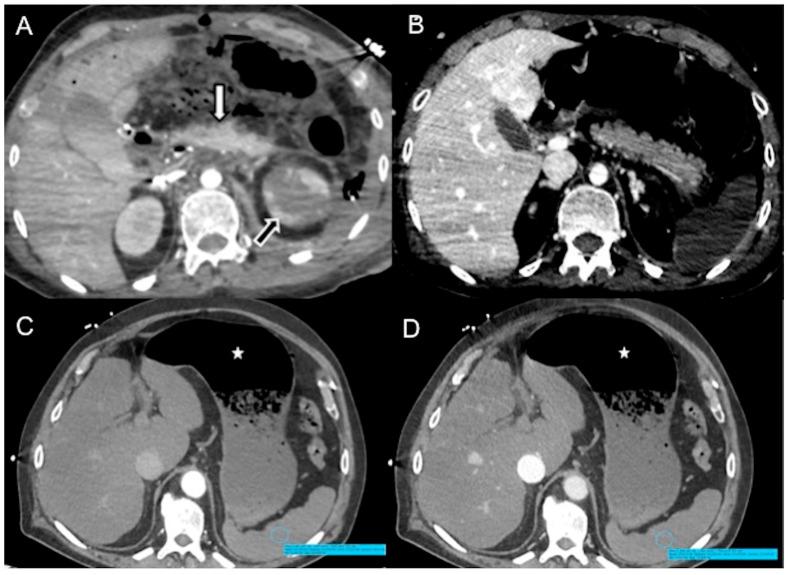

A severe mismatch between the supply and demand of oxygen is the common sequela of all types of shock, which present a mortality of up to 80%. Various organs play a protective role in shock and contribute to whole-body homeostasis. The ever-increasing number of multidetector CT examinations in severely ill and sometimes unstable patients leads to more frequently encountered findings leading to imminent death, together called "hypovolemic shock complex". Features on CT include dense opacification of the right heart and major systemic veins, venous layering of contrast material and blood, densely opacified parenchyma in the right hepatic lobe, decreased enhancement of the abdominal organ, a dense pulmonary artery, contrast pooling in dependent lungs, and contrast stasis in pulmonary veins. These findings are biomarkers and prognostic indicators of paramount importance which stratify risk and improve patient outcomes. In this review, we illustrate the various CT patterns in shock and review the spectrum and prognostic significance of thoraco-abdominal vascular and visceral alarming signs of impending death with the intention of increasing awareness among radiologists and radiographers to prepare for immediate resuscitation when required.

氧供需严重不匹配是各类休克的常见后遗症,其死亡率高达80%。各种器官在休克中发挥保护作用并有助于维持全身内环境稳定。在重症且有时不稳定的患者中,多排CT检查数量不断增加,导致更多常出现的即将死亡的影像学表现,统称为“低血容量性休克综合征”。CT表现包括右心和主要体静脉致密强化、对比剂与血液的静脉分层、右肝叶实质致密强化、腹部器官强化减弱、肺动脉致密、下垂肺野对比剂积聚以及肺静脉对比剂滞留。这些表现是极其重要的生物标志物和预后指标,可对风险进行分层并改善患者预后。在本综述中,我们阐述了休克中的各种CT表现模式,并回顾了胸腹部血管及内脏即将死亡的警示征象的范围和预后意义,旨在提高放射科医生和放射技师的认识,以便在需要时为立即复苏做好准备。